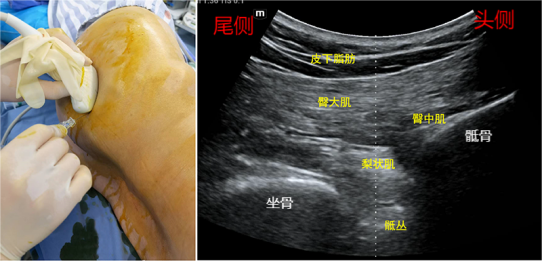

(一)后路骶丛:长轴入路法

超声准备:低频探头,深度6-10cm。体位:侧卧位。

解剖关键点:髂后上棘、股骨大转子,臀大肌、梨状肌、坐骨大孔。

扫查方法:探头平行放置在髂后上棘与股骨大转子连线中点内上二分之一处,该处深面可见臀中肌与髂骨间的臀上动脉。探头向内、向远端做滑动和倾斜这两个动作,当骨皮质连续性中断时,为坐骨大孔切迹,长条形高亮回声结构即为骶丛神经,骶丛的上方为梨状肌。此时如果探头继续往下,稍旋转或倾斜探头,也可以看到延续的坐骨神经。

穿刺方法:平面内法,建议从大腿外侧向内侧进针,在到达梨状肌深面时注射局麻药即可。注药过程中,需要注意避开下方延续的坐骨神经,避免穿通神经和神经内注射,避开梨状肌上方的臀上动脉和下方的臀下动脉。同时在此处注药包裹整个神经难度很大,不作为追求目标。

注意该入路的进针方式,亦可从大腿内侧向外侧进针。

药物用量:0.375%-0.5%罗哌卡因15-20ml。